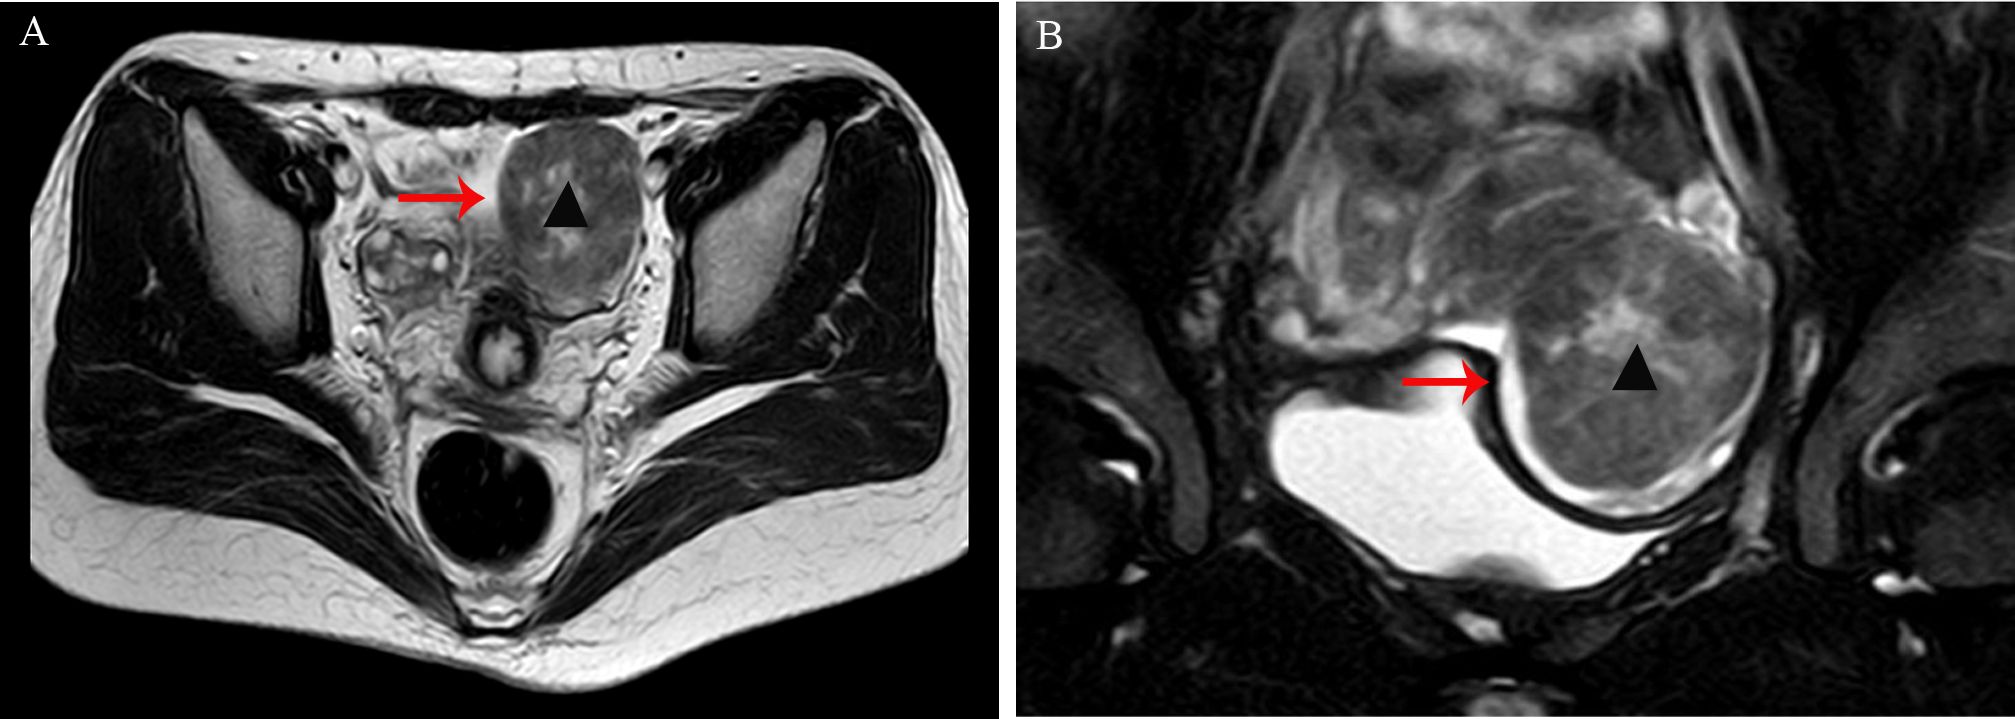

A 33-year-old woman (gravida 1, para 1) was found to have a solid mass in the left adnexal region during an incidental examination two years earlier; she remained asymptomatic throughout this period. Initial ultrasonography demonstrated a hypoechoic mass within the left ovary measuring approximately 35×31mm, with well-defined margins, heterogeneous internal echogenicity, and peripheral linear vascular signals. Serial monitoring revealed progressive enlargement of the tumor to 53×48mm, accompanied by increased vascularity (resistance index [RI]: 0.53). Pelvic magnetic resonance imaging (MRI) revealed a well-circumscribed mass anterolateral to the uterus, measuring 49×51×55mm, with mildly reduced T2 signal intensity (Figure 1). Serum tumor markers, including CA125, HE-4, CA19-9, AFP, and CEA, were all within normal reference ranges.

(A, B) Pelvic magnetic resonance imaging (MRI) revealed a well-circumscribed mass anterolateral to the uterus, measuring 49×51×55mm, with mildly reduced T2 signal intensity (arrow, indicated by ▴).